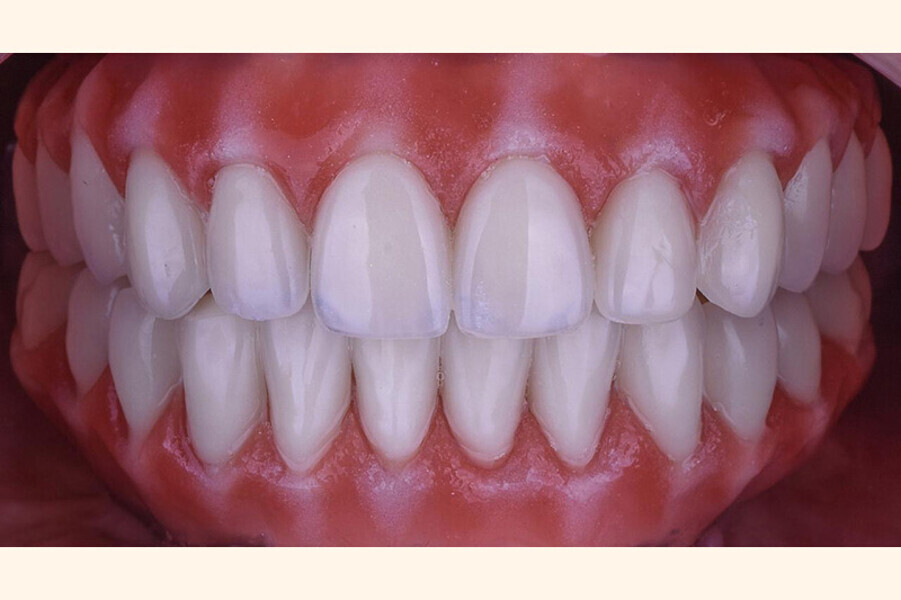

Fig. 5. Prótesis Híbrida inmediata y radiografía control con 6 años post-operatorio

Fig. 6. Prótesis Híbrida inmediata y radiografía control con 6 años post-operatorio